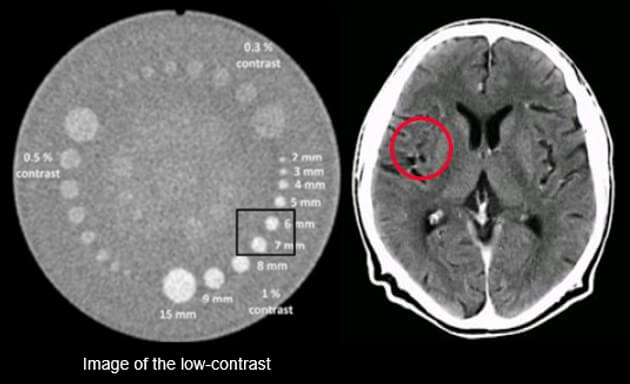

Contrast resolution allows the differentiation of small structures depending on their densities.

Contrast resolution is measured in line pairs per centimeters. It is how it differentiates between two objects. There is high-contrast resolution, cross-plane resolution, and low contrast resolution.

Low contrast objects may require a larger pixel size so that the detectors can provide sufficient data for a visible difference but the total resolution is reduced.

This image shows the effect of the kVp on image contrast. Note the differences between 100 and 120 kVP. The higher the kVp, the lower the contrast, known as low contrast resolution.

Low contrast detection is used to examine structures with low contrast such as the brain or the abdomen. This is accomplished by using higher kVp.

CR and Slice Thickness

These images demonstrate that the thicker the slice, the lower the contrast resolution. Although in general, an image with a thicker slice contains more x-ray photons (or less noise), the partial volume effect can reduce the visibility of smaller objects.